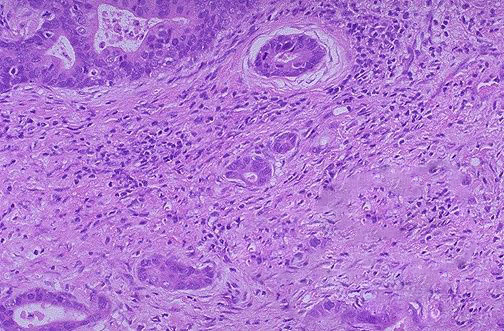

在有明显淀粉样纤维沉积的消化管管壁,肉眼观察可见整个管壁变硬、肥厚、缺乏弹性,浆膜面有不少小颗粒隆起。上述变化有时不一定累及整个消化管,而是呈现节段性分布,有时可表现一部分肠管明显扩张。组织学观察大多限于尸检病例。消化管各层都可见到淀粉样纤维沉积,以黏膜下组织的血管壁最明显,其次为固有肌层及黏膜层。淀粉样纤维沉积的血管壁肥厚,腔狭窄,血管周围的结缔组织也可看到淀粉样纤维沉积。特别在肿块形成和管壁肥厚明显的部位,固有肌层的淀粉样沉积显著。

胃、小肠、大肠的淀粉样纤维沉积程度在各型之间以及个体之间存有差异,以原发性及伴随骨髓瘤性淀粉样变病者明显,而在FAP患者较轻。从部位上看,胃、小肠的淀粉样沉积,黏膜固有层的沉积也比较明显。在原发性淀粉样变病及FAP中,胃黏膜内淀粉样纤维沉积较大肠严重。